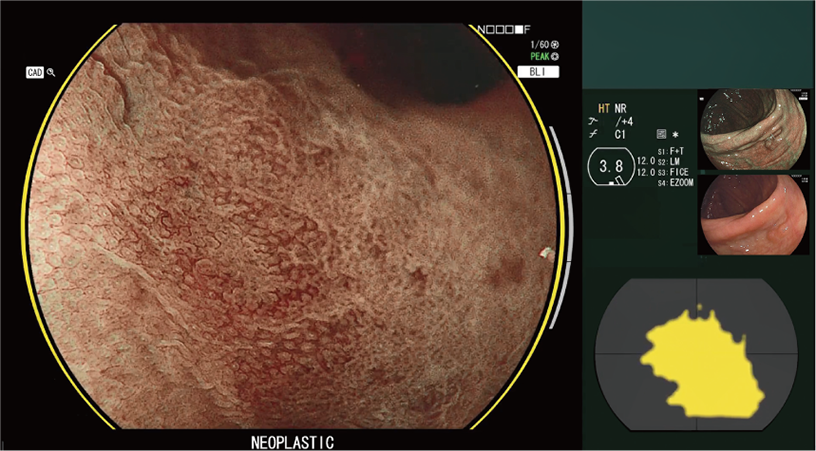

CAD EYE is FUJIFILM's brand name of computer-aided diagnosis (CAD) function for endoscopy. CAD EYE has been developed utilizing AI deep learning technology with an immense amount of clinical images.

Characterization